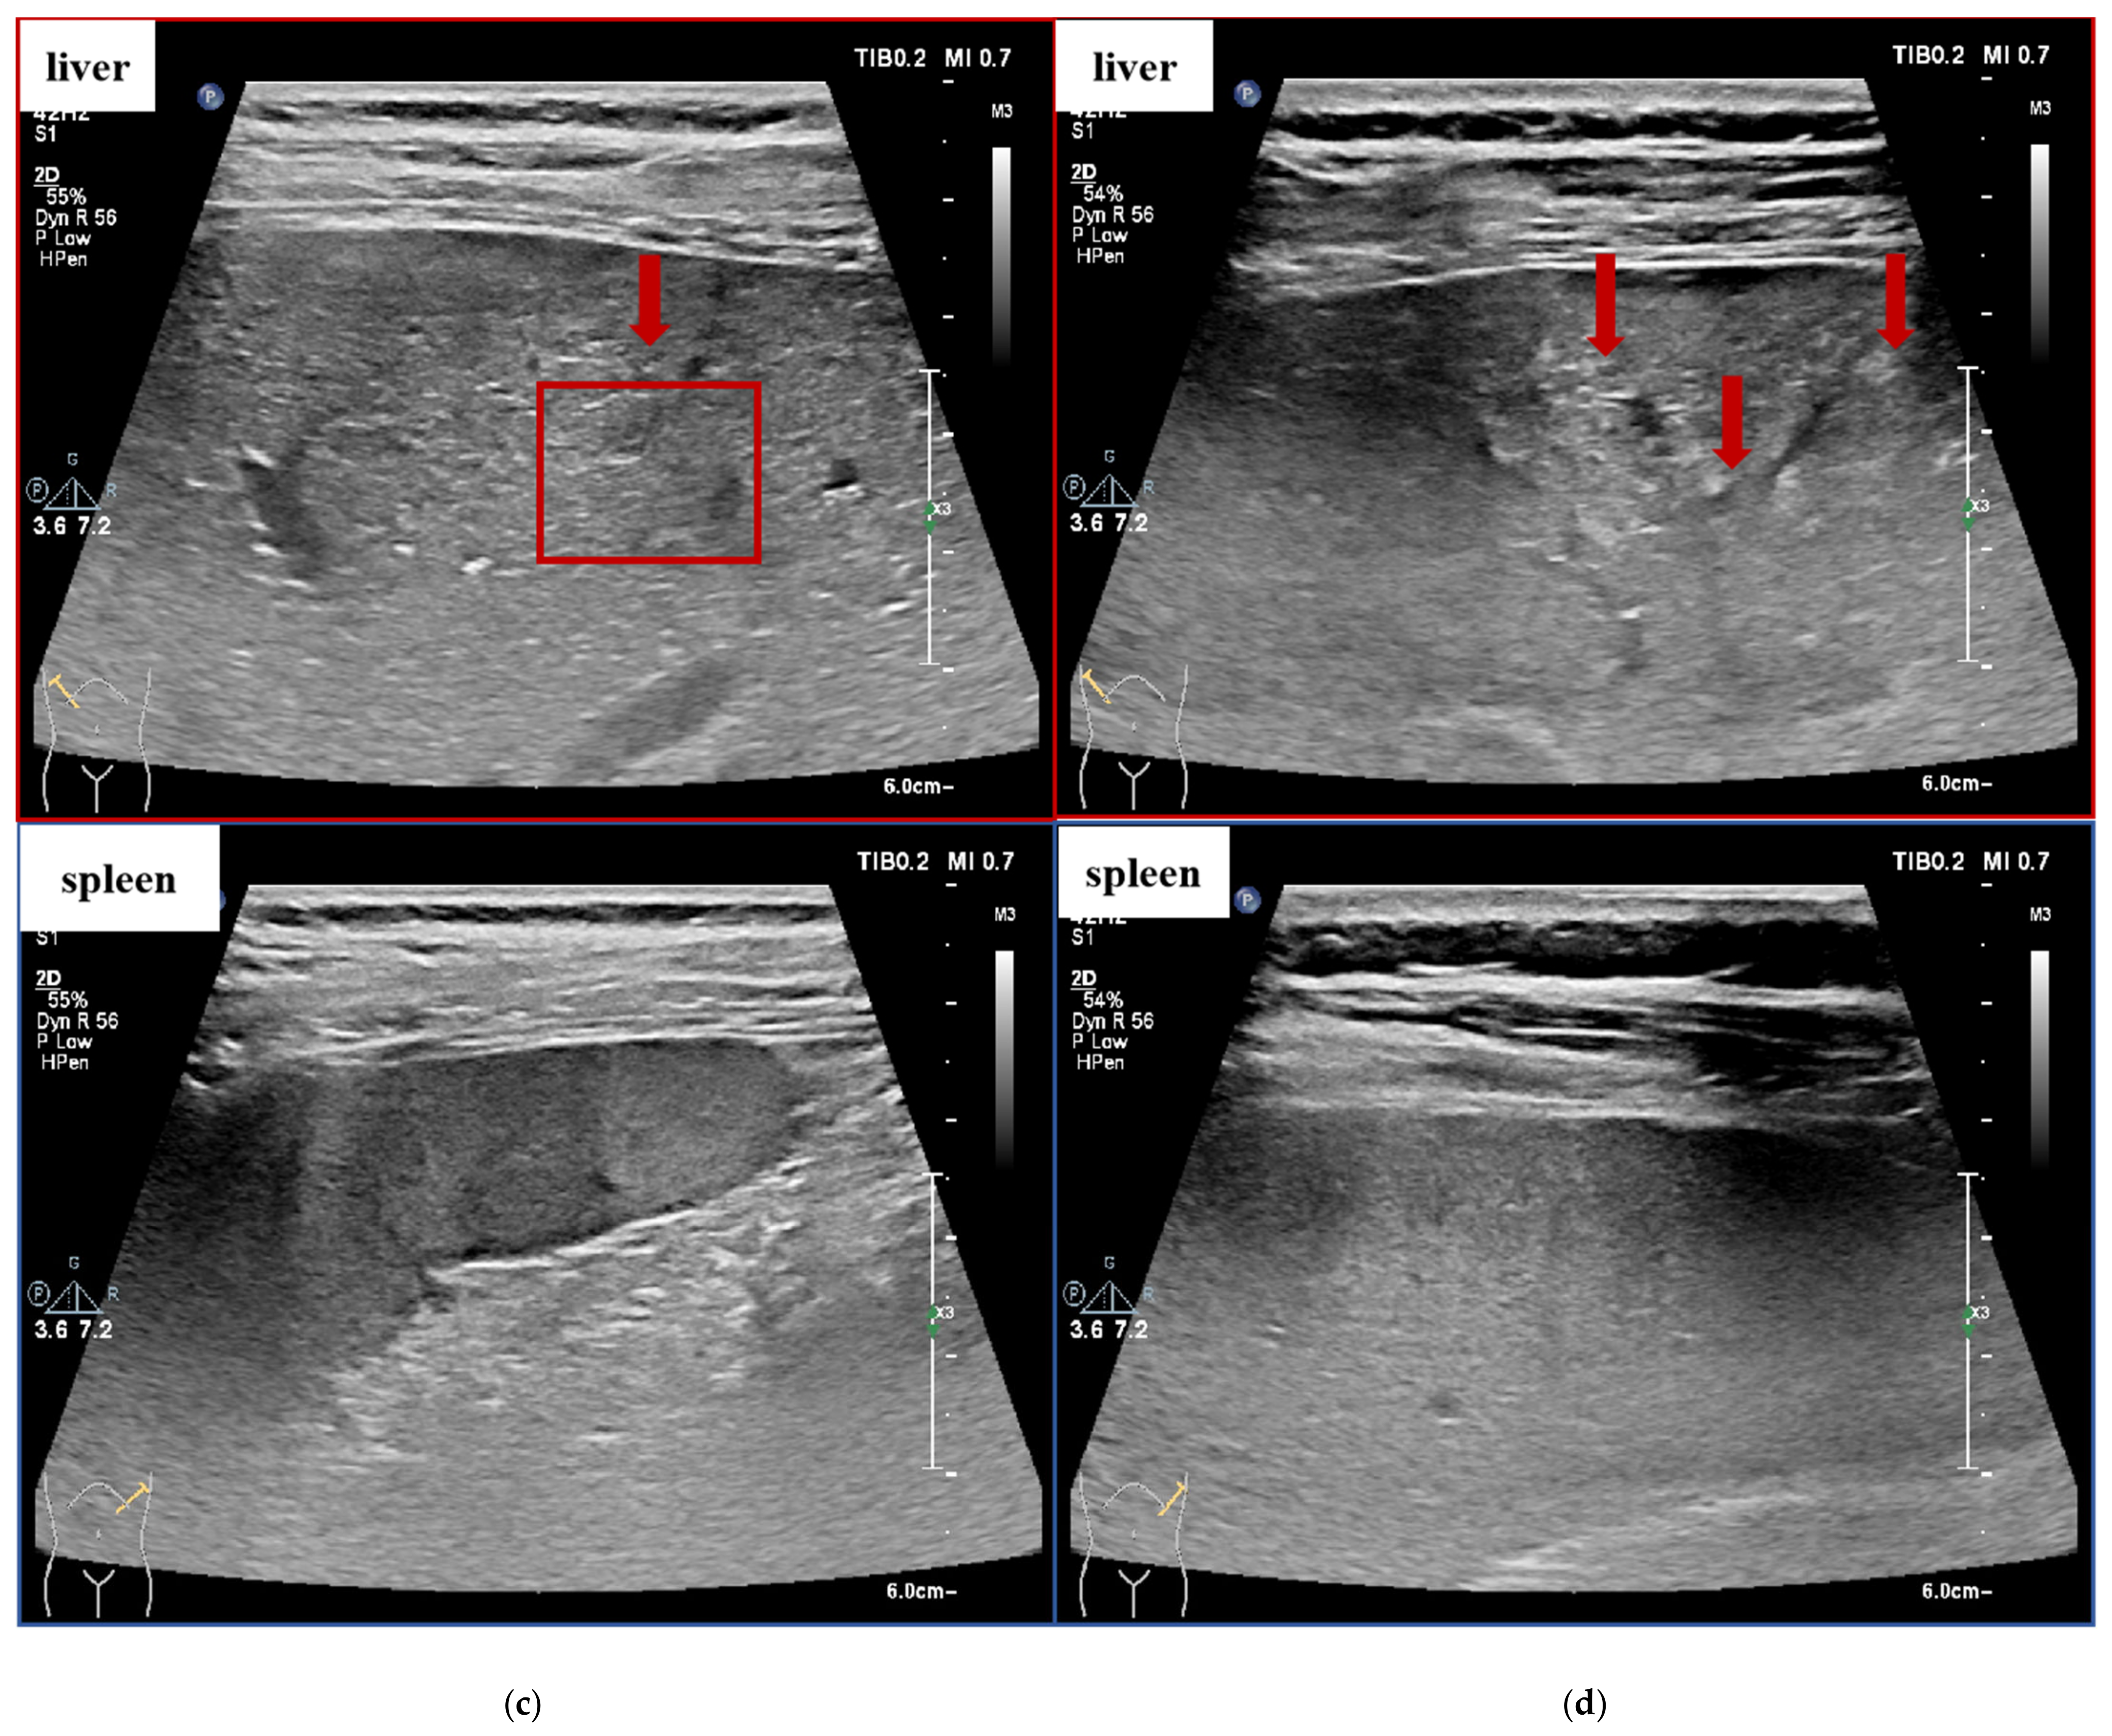

| Grade | Ultrasound Image Signs |

|---|---|

| 0 | Normal liver size, smooth liver capsule, homogeneous or slightly rough echo of liver parenchyma, clear vascular orientation, without splenomegaly. |

| 1 | Normal liver size, smooth liver capsule, rough echo of liver parenchyma, clear vascular orientation, without splenomegaly. |

| 2 | Moderate liver size, smooth liver capsule, significantly rough and enhanced echo of liver parenchyma, visible brightened linear structure shown as “strip pattern”, still clear vascular orientation, without splenomegaly. |

| 3 | Moderate or slightly smaller liver size, unsmooth liver capsule, significantly rough and enhanced echo of liver parenchyma with uneven distribution, with or without hyperplasia nodules, vague vascular terminals, with or without splenomegaly. |

| 4 | Smaller liver size, wavy liver capsule, significantly rough and unevenly enhanced echo of liver parenchyma, visible patchy enhancement, with or without nodules, variant vascular stenosis, with or without splenomegaly. |